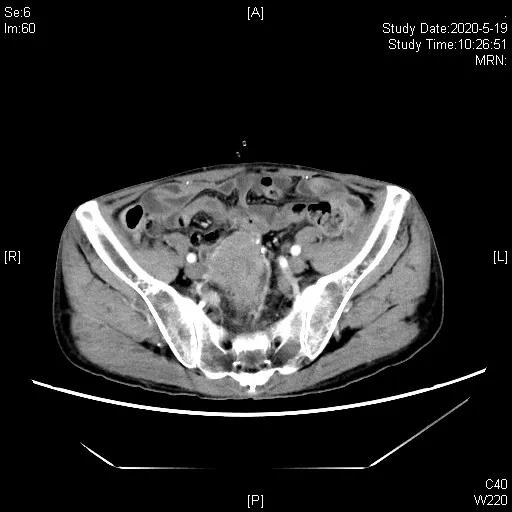

患者二线治疗后进展,TMB>10,拟行免疫治疗,鉴于患者应用抗生素不足1月(末次使用抗生素时间2020.2.20),于2020-03-25、04-21 “吉西他滨1.4d1,1.2gd8+奥沙利铂200mg”化疗2程,并于2020-03-25起,开始予以补充益生菌、调节肠道菌群联合代谢调理治疗等处理。2020-05-19,胸腹部CT示代膀胱壁增厚伴软组织肿块形成,伴双侧输尿管盆腔段受侵、双肾积水,考虑术后复发,肿块较2020-01-16老片增大,近期疗效评估疾病进展(PD),造瘘口有出血。

三线治疗3周期后,影像学评估缩小,PR